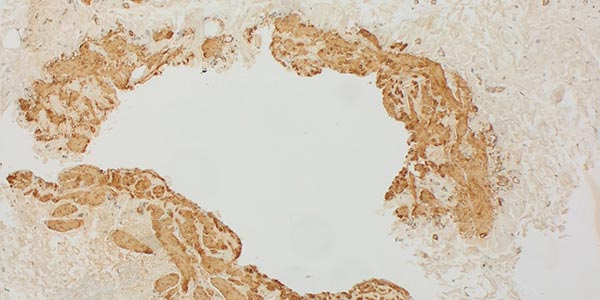

Immunhistologische Färbung auf Podoplanin mit D2-40-Antikörpern, 110-fache Vergrößerung. Das Endothel des großen dysplastischen Gefäßraums ist nicht D2-40-positiv (venöse Malformation, Ausschnitt unten rechts). Einzelne kleinere dysplastische Gefäßraume dagegen (Ausschnitt oben rechts) färben dagegen mit D2-40 an (lymphatische Malformation). Zwar liegen oft auch einzelne physiologische Lymphgefäße innerhalb einer Läsion, die Anzahl ist jedoch normal nicht so erhöht wie hier. Damit liegt hier eine kombinierte venolymphatische Malformation histologisch vor.

D2-40-Antikörperfärbung, 200-fache Vergrößerung. In dem hier dargestellten Abschnitt der Läsion ist das Endothel des großen dysplastischen Gefäßraums klar nicht D2-40-positiv und stellt damit keinen Lymphatischen, sondern einen venösen Malformationsanteil dar. Die wenigen mit dargestellten kleinen Gefäßräume mit D2-40-positiven Endothelzellen sind von Größe und Anzahl alleine nicht als pathologisch zu werten, damit eher physiologische Lymphgefäße.

Die histopathologische Aufarbeitung zeigte dann auch den typischen Befund einer benignen Gefäßläsion (CD31-positiv) mit dysplastischem, asymmetrisch unregelmäßigem Wandaufbau. Wie für solche Slow-flow-Gefäßmalformationen typisch, ist die glattmuskuläre Gefäßwand nicht überall gleich dick und symmetrisch ausgebildet, sondern fehlt zum Teil sogar ganz (SMA, EvG). Kaum Proliferation des beteiligten Gewebes (Ki67 sehr niedrig). Die fehlende WT1-Positivität der betroffenen Gefäßendothelien ist ein weiterer Hinweis auf eine Gefäßmalformation. Wesentlichstes histopathologisches Unterscheidungsmerkmal zwischen einer lymphatischen Malformation und einer venösen Malformation ist die immunhistochemische Anfärbung des Podoplanin der Gefäßendothelien der Läsion mittels des Antikörpers D2-40. Nur die Gefäßendothelzellen einer lymphatischen Malformation (D2-40 positiv) färben hier an. In dem Präparat zeigten sich zusätzlich auch multiple dysplastische Gefäßmalformationsareale, deren Gefäßendothel nicht mit D2-40 anfärbte, also handelte es sich hierbei um Anteile einer venösen Malformation. Die korrekte histopathologische Diagnose ist daher auch eine kombinierte venolymphatische Malformation. Die klinisch und in der Bildgebung klar im Vordergrund stehende lymphatische Komponente steht in dem Präparat der hier gewonnenen Stanzbiopsie aus der Läsion gegenüber der venösen Komponente eher im Hintergrund.